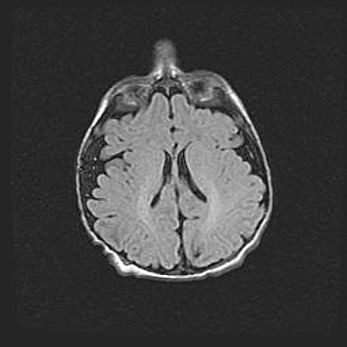

Наружная гидроцефалия с возможной атрофией височных областей.

Возраст: 28 дней

Вес: 3670 г

Пол: мужской

Окружность головы: 38 см

Срок гестации: 40 недель

Гидроцефалия головного мозга у новорожденных – это заболевание, которое характеризуется скоплением избыточного количества спинномозговой жидкости в желудочковой системе головного мозга в результате затруднения её перемещения от места выработки к месту поглощения в кровеносную систему или вследствие нарушения абсорбции. При открытой наружной форме гидроцефалии у новорожденных расширяются и переполняются субарахноидные пространства.

При нормотензивных  формах,  которые,  как  правило,  являются  следствием  перенесенных ишемических  повреждений  паренхимы  мозга,  возможно  сочетание микроцефалии  с нормотензивной гидроцефалией. В основе данных изменений лежит атрофия больших полушарий с преимущественной  локализацией  в  лобно-височных  областях.